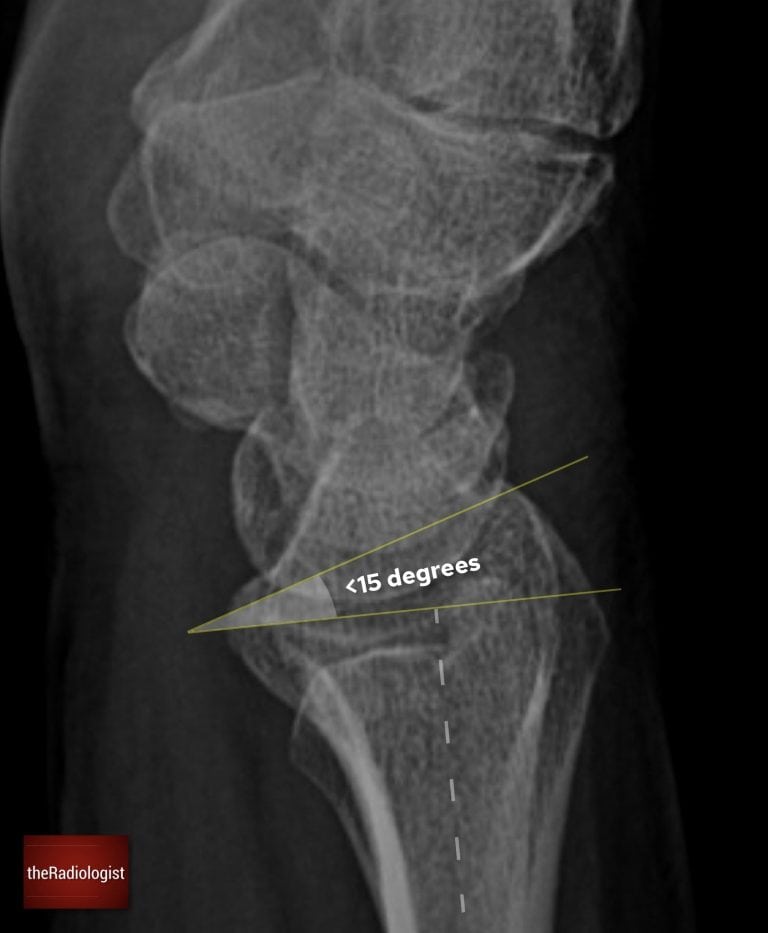

Firstly have a look to see if there is a normal volar (or palmar) tilt. If you draw a line perpendicular to the shaft of the radius and one between the dorsal and palmar tips of the distal radius, the angle between these should be less than 15 degrees. If more this could be related to an unstable fracture or DISI (see below).

Check for a normal volar (palmar) tilt on a lateral wrist X-Ray